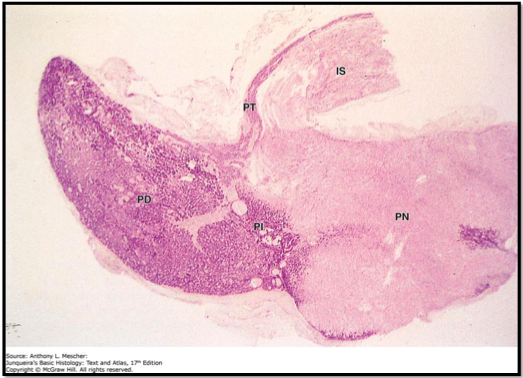

identify anterior and posterior pituitary tissue

A

parts of anterior pituitary

pars distalis, pars tuberalis, pars intermedia

Q

infundibulum, pars nervosa